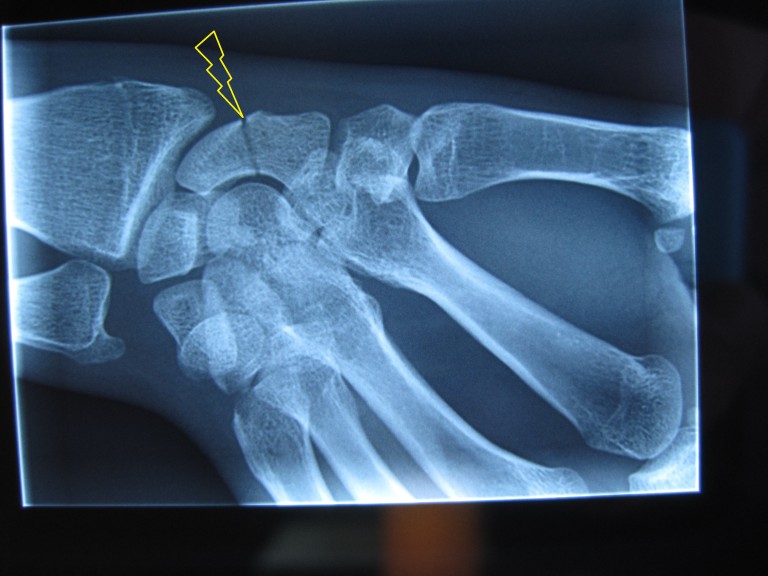

Fracture du scaphoïde Fiche santé HCL Le temps de reconsolidation de cet os assez mal vascularisé est long et varie en fonction des différents types de fractures et du traitement mis en place Une étude a constaté que les plâtres en cas de fracture du scaphoïde génaient la conduite automobile Le temps de reconsolidation de cet os assez mal vascularisé est long et varie en fonction des différents types de fractures et du traitement mis en place

Source: mannlichmls.pages.dev Fracture du scaphoïde Urgences de la main à Paris , Le temps de guérison va dépendre du type de fracture et du fait qu'elle soit déplacée Une fracture scaphoïde non déplacée, c'est-à-dire sans diastasis interfragmentaire, nécessite un temps de guérison moindre que dans le cas d'un déplacement ou d'une fracture du pôle proximal impliquant une chirurgie

Source: ckirschzbw.pages.dev Fracture du cassé) temps de guérison & avis kiné , En général, on estime que l'os prendra entre 8 à 12 semaines avant de guérir. Le tiers distal devrait guérir en 6-8 semaines, le tiers moyen en 8-12 semaines et le tiers proximal en 12-24 semaines

Source: tostaquieji.pages.dev Fracture clavicule Clavicule cassée Temps de guérison Conseil , Le délai de consolidation varie en fonction de la localisation de la fracture Le scaphoïde est l'un des 8 os constitutifs du carpe, à la base du poignet, et ses fractures sont extrêmement fréquentes